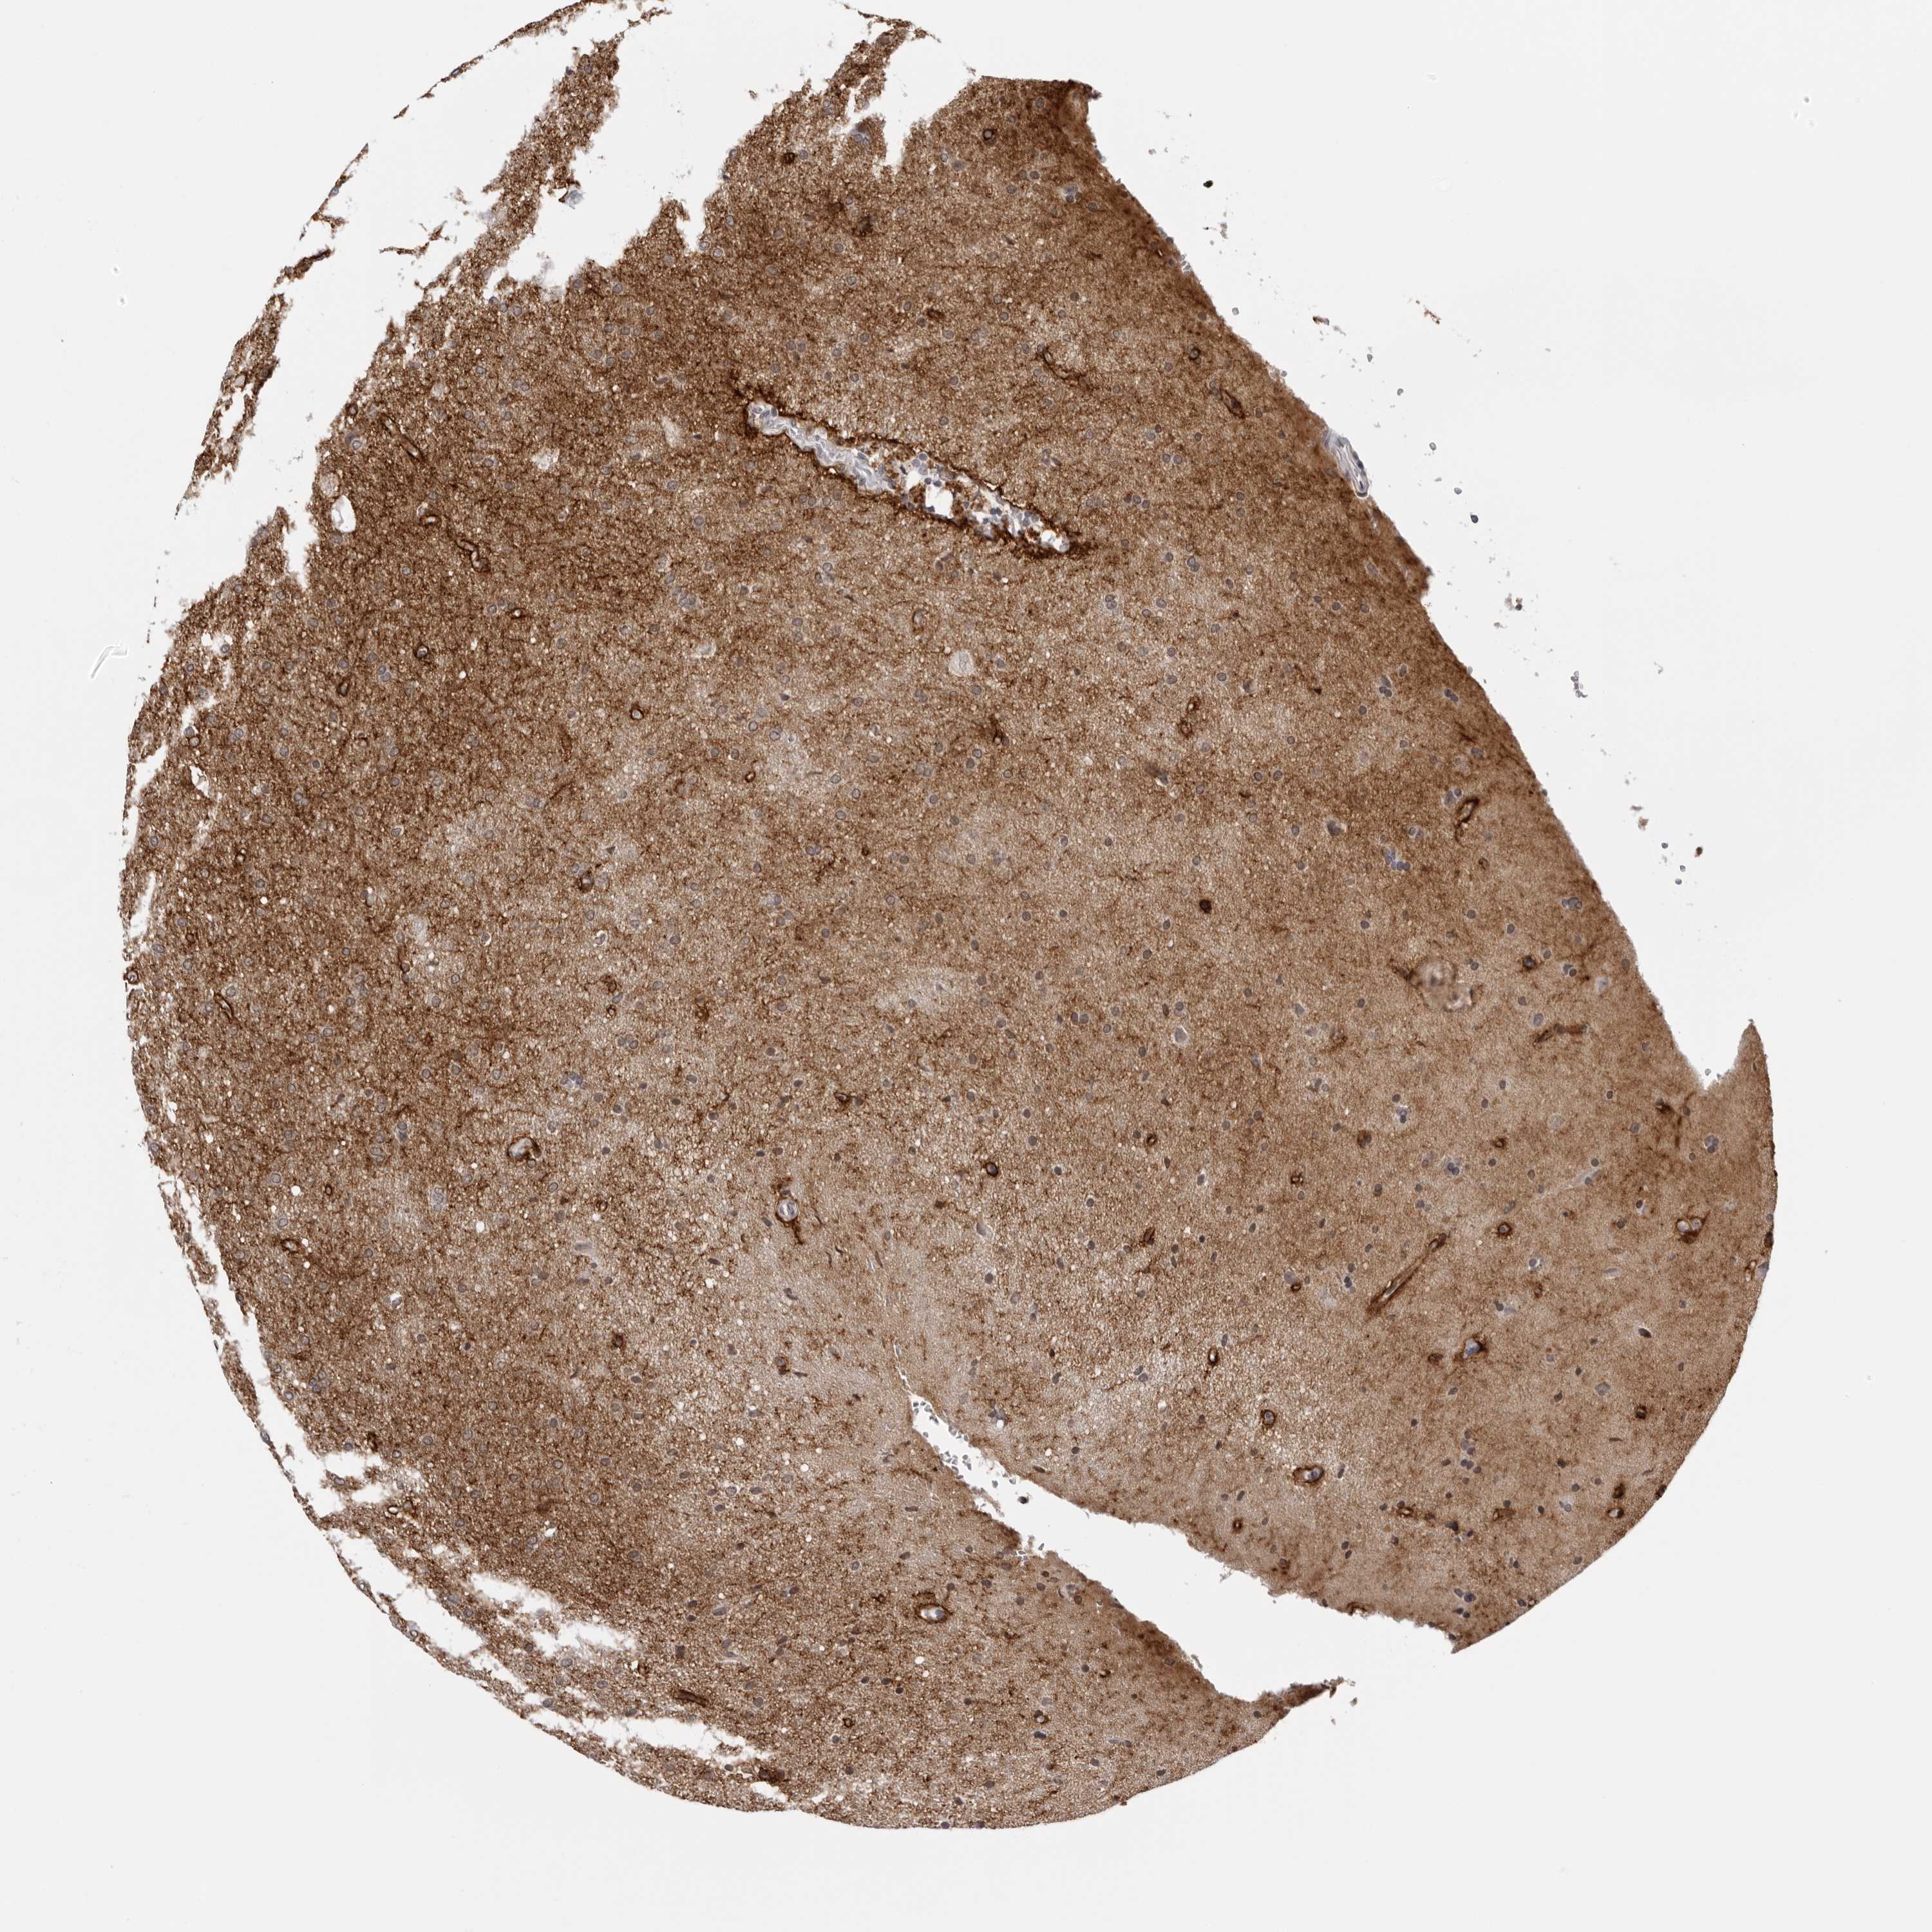

GLIOMA - Protein expressioni

A mouse-over function shows sample information and annotation data. Click on an image to view it in a full screen mode. Samples can be filtered based on level of antibody staining by selecting one or several of the following categories: high, medium, low and not detected. The assay and annotation is described here.

Note that samples used for immunohistochemistry by the Human Protein Atlas do not correspond to samples in the TCGA dataset.

Antibody stainingi

Antibody staining in the annotated cell types in the current human tissue is reported as not detected, low, medium, or high, based on conventional immunohistochemistry profiling in selected tissues. This score is based on the combination of the staining intensity and fraction of stained cells.

Each image is clickable and will lead to virtual microscopy that enables deeper exploration of all samples and also displays staining intensity scores, fraction scores and subcellular localization as well as patient and tissue information for each sample.

Antibody HPA028411

Staining

High

Medium

Low

Not detected

Intensity

Strong

Moderate

Weak

Negative

Quantity

>75%

75%-25%

<25%

None

Location

Nuclear

Cytoplasmic/membranous

Cytoplasmic/membranous,nuclear

Glioma, malignant, High grade

Glioma, malignant, Low grade